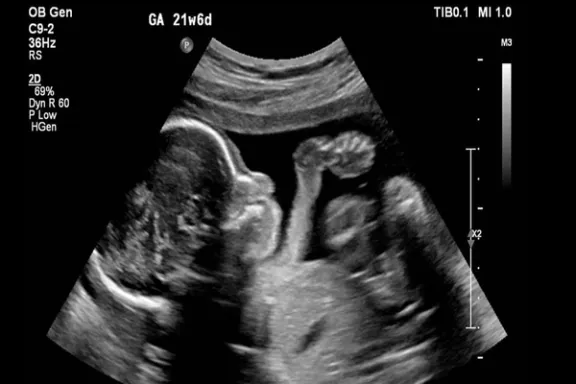

مصرف فلوکستین در دوران بارداری، خطری برای رشد مغز نوزادان

یک مطالعه جدید نشان داد مصرف داروی ضدافسردگی از سوی مادران باردار میتواند منجر به ناهنجاریهای بلند مدت در مغز کودکان شود.

پژوهشگران ایتالیایی و فنلاندی در پژوهشی تازه دریافتند مصرف داروی ضد افسردگی فلوکستین، معروف به پروزاک، در دوران بارداری و شیردهی میتواند رشد طبیعی مغز نوزادان را مختل کند و آنها را در معرض خطر ابتلا به افسردگی و اختلالات حافظه قرار دهد.

به گزارش دیلی میل، این یافتهها که در نشریه «مولکولار سایکایتری» منتشر شد، حاکی از آن است که هر گونه اختلال در روند زمانبندی شده و حساس رشد مغز جنین میتواند آسیبهای ماندگاری به ساختار مغز وارد کند؛ هرچند علائم آن ممکن است در بزرگسالی ظاهر شود.